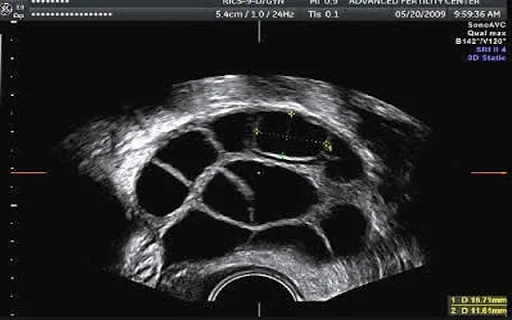

Пункция происходит, когда яичник такой:

Пунктируются маленькие фолликулы, в которых не зрелые яйцеклетки. Далее с помощью волшебства эмбриологии и специальных сред они дозревают и замораживаются уже зрелые клетки.